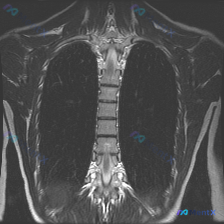

资料背景是:一张胸部MRI T2加权像(冠状位),临床核心诉求是排查脊柱侧弯。

- 肺实质、纵隔、胸膜腔、胸壁软组织都未见明显异常信号或占位

- 报告写了“胸椎椎体及附件形态基本完整”、“脊柱旁软组织未见明显异常”

- 没有提到骨质破坏、椎间盘异常信号、脊髓信号异常

但问题在于:这份报告对“脊柱排列”的描述非常模糊,甚至没提冠状面的力线情况。